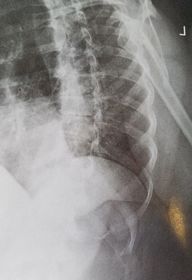

| PA Ribs Below Diaphragm Unilateral | Excessive obliquity |

| Left thorax is more anterior | |

| Right thorax is more anterior | |